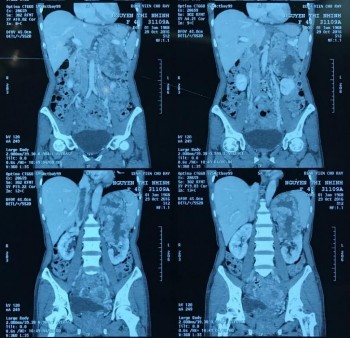

Phim CT scan bướu TTT bên trái có chồi bướu trong TM chủ dưới

[Nguyễn Thị N., 36 tuổi, SNV: 2160102149]

Bệnh phẩm ung thư biểu mô vỏ TTT, thận trái và chồi bướu

Ghi chú: mô tả TM chủ dưới và TM thận 2 bên sau khi cắt thận trái và bướu TTT trái thành 1 khối.